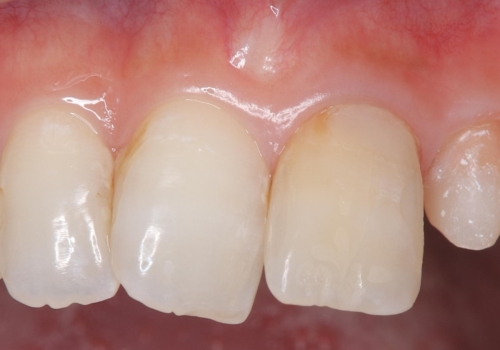

外れ欠けている土台をまずやり替えた後、根管治療後の緊密な封鎖を目的としオールセラミッククラウンをセットしました。